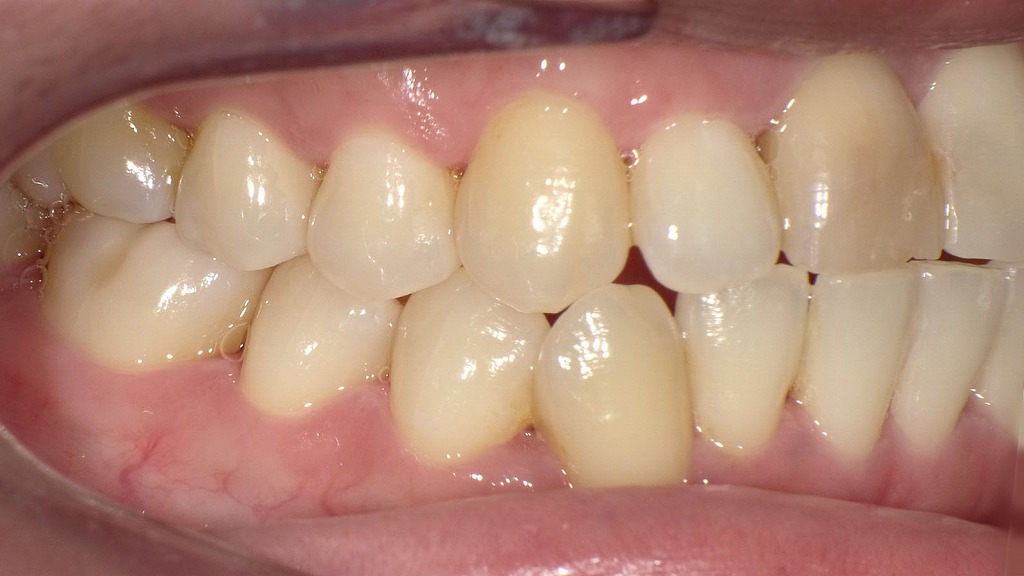

左(または上)の画像では、歯ぐきの縁や歯周ポケット内に歯石が付着し、細菌が増殖しやすい状態が確認できます。

歯石は口臭の原因となるガスを発生させ、歯周病の進行や不快なネバつきの原因にもなります。

右(または下)の画像は、歯石除去(スケーリング)後の状態です。

歯石と細菌性バイオフィルムが除去され、歯面が清潔になり、歯ぐきの炎症や口臭の原因が改善しています。

口臭対策には、セルフケアだけでなく、定期的なプロフェッショナルクリーニングが重要です。